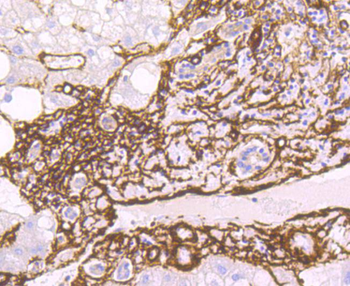

FC, ICC, IF, IHC-Fr, IHC-P, WB

Human

Mouse

Rabbit

Recombinant

Unconjugated

50 μl, 100 μl - MARK3 Recombinant Rabbit Monoclonal Antibody [orb704310]Featured